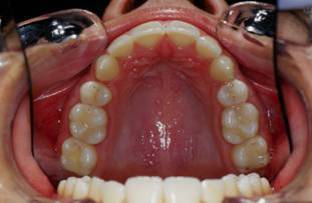

Suite et fin.

Il faut preciser une chose: Suivre un cas sur le forum ce n'est pas pareil comme vivre ce cas pendant le traitement. Le sourir fige sur photoo n'est pas aussi expressif et reel comme en clinic. La pression mise par les parents parfois est tellemnt forte qu'on finit par ceder.

Voila la fin de l'histoire...

17 hfdocf - Eugenol

18 aotm1c - Eugenol